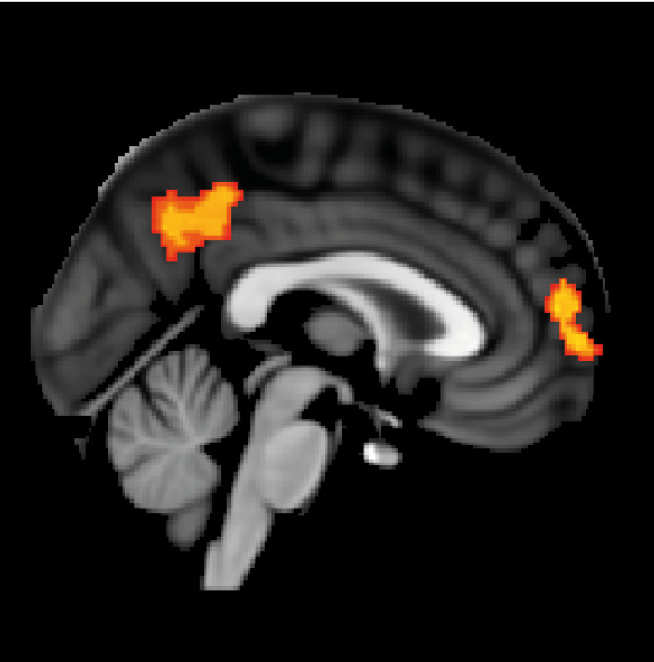

They found that differences in the makeup of the brain’s white matter – the tissue deep in the brain and rich in the branching ‘tails’ of nerve cells – were key. The research revealed that those who had more connectivity in the regions being stimulated were more likely to respond better to the treatment.

However, when they analysed MRI scans, they found that those participants with highly-connected white matter in the brain region being stimulated responded best to the treatment, and those who had damaged or less-connected regions of white matter showed less improvement.